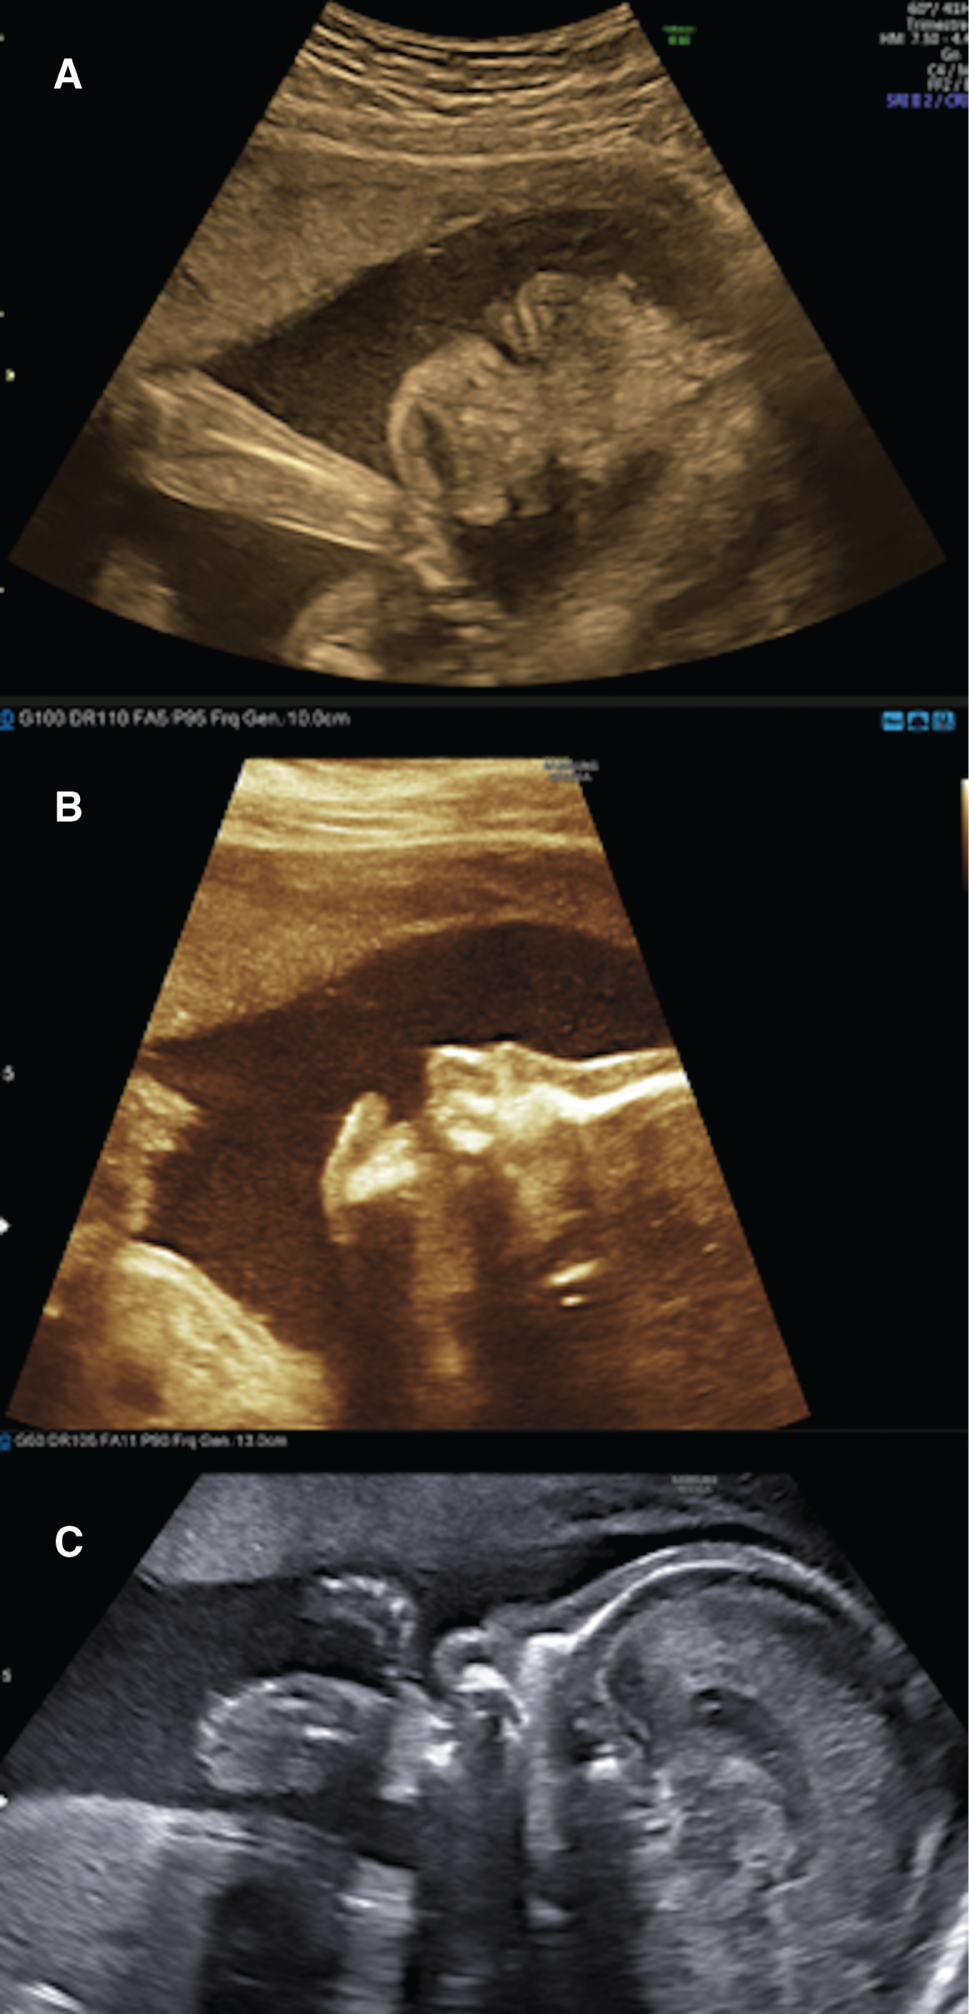

After a normal first trimester ultrasound, a 20-year-old primigravida woman was diagnosed at 27 weeks of gestational age (GA) with fetal growth restriction (FGR). The estimated fetal weight was at the 0.7th percentile. The fetus had facial dysmorphism with the mouth constantly open as an eclabium, hypoplastic nose (Figure 1), intragastric hyperechoic content (Figure 2) and skin scaling with skin particles floating in the amniotic liquid (Figure 3). The amniotic liquid was slightly hyperechoic with sedimentation of skin scales observed by vaginal ultrasound (Figure 4). No visceral abnormality was found. The amniocentesis performed showed an alpha-fetoprotein increased ten-fold (60,500 μg/L). Those findings recall a severe congenital ichthyosis and termination of pregnancy was proposed, but refused. Within several weeks we observed progressively fetal immobilism and hydramnios. At 30 weeks of GA corticosteroids prophylaxis and tocolytics were administrated to prevent premature delivery secondary to uterine contractions due to hydramnios. At 31 weeks of GA the patient gave birth to a baby boy of 1380 g, 40 cm of height and 28 cm of cranial circumference and normal cord blood pH. The Apgar score was 3–3–3. The baby boy had severe ichthyosis, atrophic ears, everted eyelids (ectropion), a hypoplastic nose, eclabium and stiffened skin surface. The couple opted for palliative care and the baby died at 33 min of life. An autopsy was refused. Comparative genomic hybridisation (CGH) array and clinical exome on cord blood were negative.

Eclabium and ectropion on the coronal axis of the face; (A) Eclabium and ectropion on the coronal axis of the face; (B) hypoplastic nasal bone and eclabium on the profile view; (C) hypoplastic nasal bone on a strictly median sagittal axis of the head (corpus callosum completely viewed).

Some authors [3], [4], [5], [6] used three-dimensional (3D) and four-dimensional (4D) analysis to better visualise the facial dysmorphism. These are diagnostic tools that we recommend using as they helped us to confirm our suspicion, and the parents to better understand the pathology.